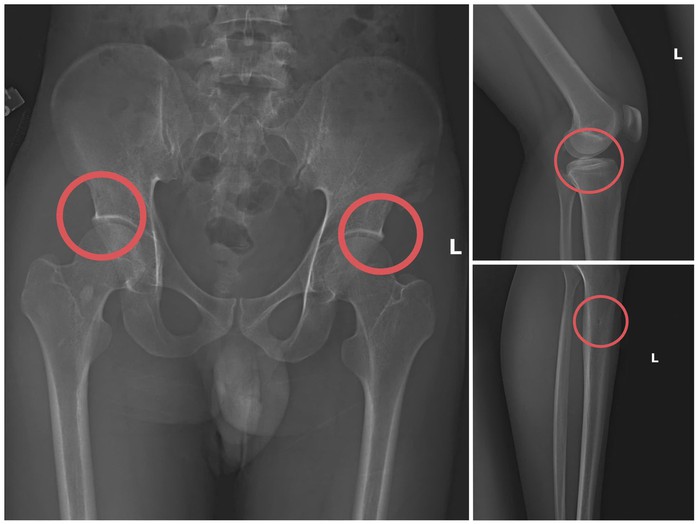

Tạ Minh Châu trực tiếp thực hiện hành vi tiêm thuốc mê, dùng búa đinh tác động vào xương người mua bảo hiểm, tạo nên các vết nứt xương tương tự tai nạn thật. Khi thương tích đã tạo xong, Châu tiếp tục hướng dẫn các đối tượng dựng hiện trường giả như điện giật ngã, trượt chân ngã suối nhằm hợp thức hóa bệnh án và hoàn thiện hồ sơ yêu cầu chi trả.

Các đối tượng dùng búa đập vào xương tạo ra thương tích để chiếm đoạt tiền của các công ty bảo hiểm. Ảnh: Công an cung cấp

Theo cơ quan công an, đây là thủ đoạn vô nhân tính, coi thường sức khỏe, tính mạng của người tham gia. Đối tượng đã tính toán kỹ để gây thương tích đúng vị trí có mức chi trả cao, khiến các công ty bảo hiểm khó phát hiện dấu hiệu gian dối.